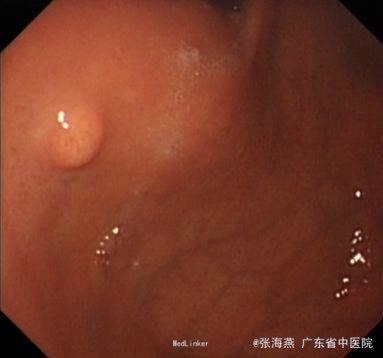

体格检查:BP:146/87mmHg;腹平坦,未见胃肠型及蠕动波,腹软,未扪及包块,上腹部轻压痛,无反跳痛,肝脾肋下未扪及,肝肾区无叩击痛,麦氏征(-),莫非氏征(-),移动性浊音(-),肠鸣音5次/分。 辅助检查:血型:B型,RhD阳性;血常规、二便常规、凝血、生化、肝功、CEA、CA199、输血4项未见异常。心电图:窦性心律,心脏逆钟向转位。胸片:主动脉硬化;胸椎退行性变。B超:胆囊壁稍毛糙,肝脏、胰腺、双肾、膀胱未见明显异常。超声胃镜:胃底固有肌层隆起:符合胃底间质瘤改变;慢性浅表性胃窦炎。

诊断:1.胃底间质瘤(ESD术后);2、慢性胃炎;3、高血压病2级;4、颈椎退行性变。 治疗:治疗上,行ESD术切除胃底肿物,术后予明可欣静滴预防感染,潘妥洛克静滴抑酸护胃,铝镁加混悬液口服保护胃粘膜,以及补液营养支持治疗。术后病理提示:符合胃肠道间质瘤(低级别,无风险);经治疗后,患者无特殊不适,予出院。